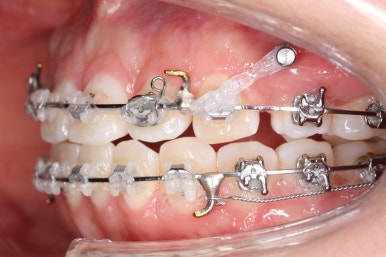

이 뽑은 틈은 거의 없어져가고 있고, 중간평가 이 후 더 필요한 위치에 미니스크류를 추가하여 당기고 밀고 밀어넣고 다양한 작업을 해주게 됩니다.

틈은 다 다물어졌고, 부가적인 정교한 마무리 과정을 더 거치게 됩니다.

중앙선도 잘 맞고 교합도 잘 마무리되었습니다.

이 뽑은 자리가 다시 벌어지지 않게 앞니가 다시 틀어지지 않게 유지철사를 부착하고 마무리를 하였습니다.